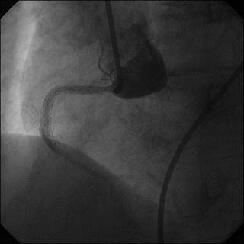

����ALCx take off lesion ��PCI���s���܂����B

�����搶�̌䏕����q�����ċ}篁A�a�i�����搶�j�ɗ���ŗ��Ē����܂����B

CBA(3.5?)+STENT(3.5�~13?)��strategy�ōs������ɂ��Ă��܂������A

�����ő��Z������܂����B

��������Stormer(3.5�~15?)��pre������STENT����悤�Ǝv������pre��distal����

�ɑ傫���Ă��܂��A���ǂ����̒ʂ�S670(3.5�~24?)������H�ڂɂȂĂ���

���܂����BCB�������炱��ȂɗȂ����������Ȃ��`�Ƃւ���ł��܂��܂����B

���҂���A�a�A�����Ă��������A�h�o�C�X�����������搶���A�\����܂���B

���x����͑O���ɂ������device�Ƀ`�F�b�N������悤�ɂ��܂��B

�ꉞ�A���ʂ�Y�t���܂��B